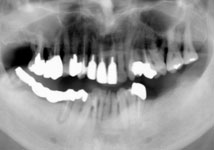

虫歯と歯周病が進行し、歯が動揺して噛みにくいということで受診されました。

歯周再生治療と審美補綴治療によってトータルコーディネートしました。

今では虫歯も治り、しっかり噛めるようになったと満足されています。 |